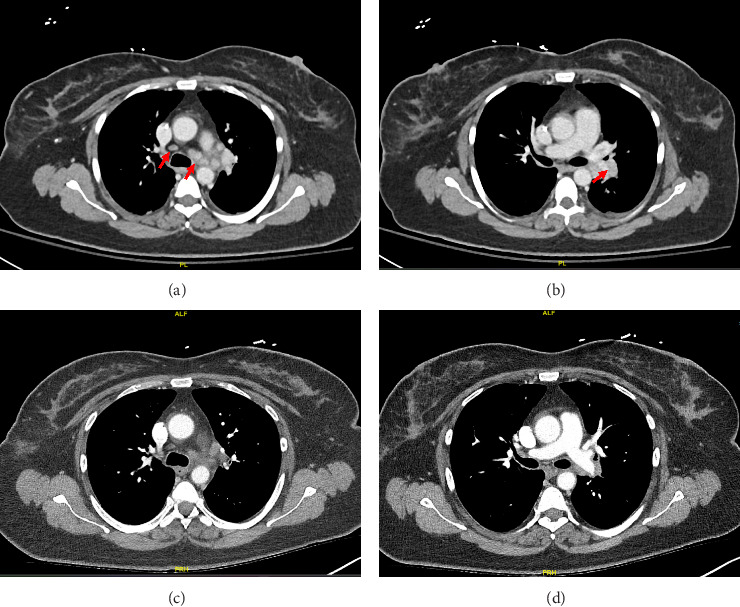

Background: Immune checkpoints are molecules that serve to augment or inhibit the immune response. The treatment landscape for numerous tumors now relies significantly on immune checkpoint inhibitors (ICIs). Pembrolizumab, a subset of ICIs specifically focused on the programmed cell death 1 (PD-1) molecule. By blocking PD-1, these inhibitors enhance the ability of the immune system to fight cancer cells. Although PD-1 inhibitors are critical in cancer treatment, their use can be associated with immune-related adverse events, such as ICI-related sarcoid-like reaction. Case Presentation: This report describes a 49-year-old female patient with stage IIIA breast cancer breast cancer who developed ICI-related sarcoid-like reaction after starting a neoadjuvant chemoimmunotherapy regimen that included Pembrolizumab. After 4 months of ongoing treatment, she started having significant nausea and vomiting. Computed tomography (CT) scans performed during hospitalization revealed multiple pathologically enlarged thoracic lymph nodes, suspicious for disease progression. Initially, the laboratory workup and cultures were unrevealing. However, esophagogastroduodenoscopy and bronchoscopy were performed, showing noncaseating granulomas in both the stomach and thoracic lymph node biopsy samples. The patient was diagnosed with a sarcoidosis-like reaction to Pembrolizumab. Notably, her symptoms rapidly improved upon initiating systemic corticosteroids. Follow-up CT scan showed a significant improvement in lymphadenopathy after discontinuing Pembrolizumab. Conclusion: This case emphasizes the significance of acknowledging sarcoid-like reactions as possible adverse effects of Pembrolizumab. Given the rising utilization of PD-1 inhibitors, it becomes imperative to be mindful of such adverse events. This awareness helps avoid misdiagnosing disease progression and aids in making informed decisions about ongoing treatment with ICIs.